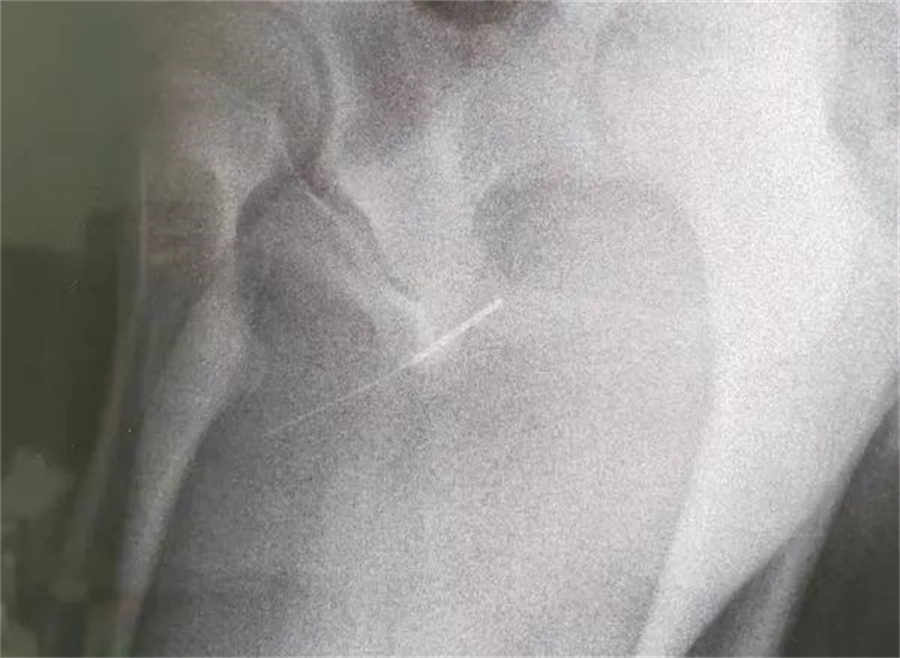

“孩子大概是中午的时候把银针塞进尿道中,因为针灸银针前段柔软纤细而末段又有增粗的螺旋状柄头,所以很难取出来。家长已经带他在当地医院拍片确诊,晚上7点多转到我们医院,当时孩子尿道口有血,疼痛难忍......”a片网站

急诊外科接诊后立即收入院并第一时间做好手术准备,此时泌尿外科主任谢方达也紧急从家中赶到了医院,经过术前检查,确认银针卡在了接近球部尿道的部位,位置比较深,又没进入到膀胱里,如何尽快地取针成为一个颇具难度的挑战。

孩子家长和泌尿外科专家都希望用最微创的方式完成手术。但因孩子年龄小、尿道细,体重又偏大而难以实现,术中医生在保证对孩子造成伤害最小的前提下,采取隐匿小切口的方式,顺利将6.5cm的银针从尿道中刺破取出,为孩子解除了困扰,术后恢复三四天后即可顺利出院。